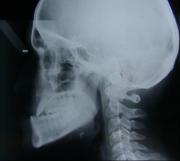

Når du er henvist til Afdeling for Kæbekirurgi, bliver du indkaldt til en forundersøgelse, hvor vi klarlægger dit behandlingsbehov og behandlingsforløb. Du skal også til en konsultation hos en specialtandlæge, hvor du får taget røntgenbilleder og tandaftryk.

Ved første besøg

Du vil blive set af en kæbekirurg og du vil få taget røntgenbilleder og/eller en scanning. Under besøget vil dit ansigt blive målt og oplysningerne tastet ind i et skema. Disse mål samt dine røntgenbilleder og/eller scanning, vil blive brugt på en efterfølgende konference, hvor der bliver lagt en ortodontisk behandlingsplan og en kirurgisk behandlingsplan.